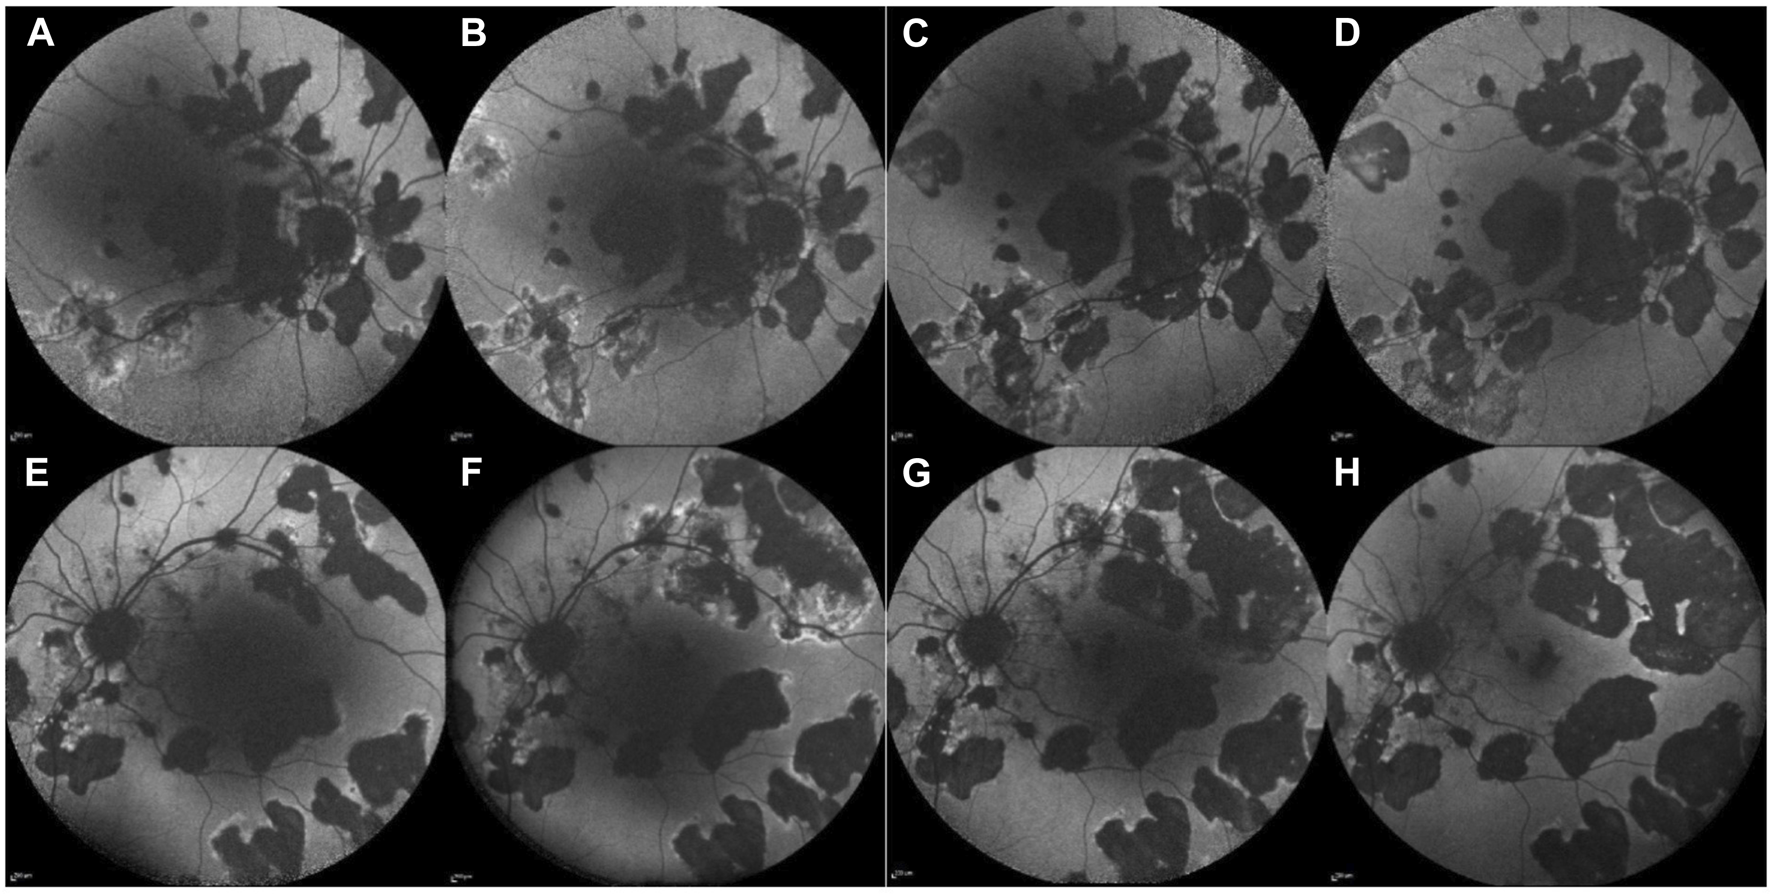

In 2018, a 59-year-old man presented with a 1-month history of decreased visual acuity and increased floaters in the LE, with a BCVA of 0.02 in the LE and 0.9 in the RE. The diagnosis of posterior uveitis was established. Slit-lamp examination revealed granulomatous endothelial precipitates, 0.5+ cells in the AC, and 2+ vitreous cells in both eyes. Both optic discs appeared hyperemic, and yellowish inflammatory retinal lesions were observed, more pronounced in the LE, with some peripheral pigmented atrophic lesions in the mid-periphery in both eyes, corresponding to irregular hyper-autofluorescent or hypo-autofluorescent lesions with an irregular hyper-autofluorescent border on fundus autofluorescence (FAF) (Figures 3A, B, E, F). FA displayed multiple early-phase hypofluorescence and peripapillary hyperfluorescence. Indocyanine green angiography (ICGA) showed corresponding hyperfluorescence. OCT revealed a peripapillary hyperreflective lesion above the retinal surface with surrounding edema. Owing to the above findings, the patient was diagnosed with ampiginous choroiditis.

Figure 3. Case 3. Fundus autofluorescence (FAF) of the RE (upper line) and LE (lower line) before JAK-i therapy (A, B, E, F) and after the initiation of JAK-i therapy (C, D, G, H). FAF images taken over 1 year (A, E) and 6 months (B, F) before the initiation of JAK-i therapy reveals numerous hypo-autofluorescent lesions with irregular hyper-autofluorescent borders, which increase in size and number over time. FAF images taken 3 months (C, G) and 9 months (D, H) after the initiation of JAK-i treatment show a reduction of the hyper-autofluorescent border and no new lesions.

Data in row 3, Table 1. Treatment began with IV boluses of 500 mg of MP daily for three consecutive days, followed by oral MP at an initial dose of 48 mg daily, and was gradually tapered to 12 mg, with the addition of various DMARDs (MP, MMF, and adalimumab). Peripapillary choroidal neovascularization (CNV) that developed in the RE before the administration of adalimumab (ADA) required multiple intravitreal anti vascular endothelial growth factor (VEGF) injections. Despite systemic treatment, inflammation persisted, and the retinal lesions increased in size, with new lesions appearing over the course of 6 months. After 3 years, ADA was replaced with 4 mg of baricitinib daily. Only the MP dose was tapered and has now been stopped completely. Nine months after commencing baricitinib the inflammation. stabilized in terms of new chorioretinal lesions – no new ones were documented.

No additional chorioretinal lesions or systemic side effects were documented during the 17-month follow-up period (Figures 3C, G after 3 months of treatment with baricitinib; Figures 3D, H after 9 months of treatment with baricitinib). His last documented BCVA on his RE was 0.4 and LE 0.5.